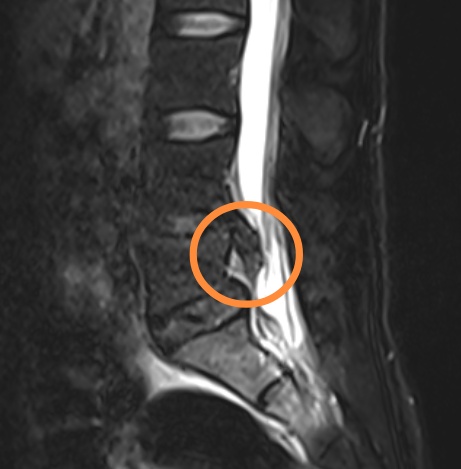

杨女士,30 岁,因长期久坐且健身方式不当(频繁进行硬拉锻炼),两年前开始出现腰痛和左腿痛。当时于我院脊柱外科蒋帅副主任医师处就诊,诊断为“腰椎间盘突出症、腰5峡部裂”,症状较轻,采取保守治疗后有所好转,但腰痛仍时有反复且逐渐加重。上个月劳累后,左腿出现放射状疼痛,输液治疗后虽有缓解,但左腿麻木严重。再次就诊后,腰椎磁共振显示椎间盘脱出并向下游离,CT显示L5椎弓根峡部断裂,X片提示腰椎不稳,经详细检查,确诊为:L4/5 巨大腰椎间盘脱出和L5 双侧腰椎峡部裂。

这两种疾病同时存在,使她的腰痛和腿痛症状雪上加霜,患者L4/5巨大的腰椎间盘脱出严重压迫了神经根,需手术干预,否则神经受压时间过长会造成更严重的神经损伤。患者腰椎峡部裂导致腰椎不稳,腰5/骶1的椎间盘变性,腰痛逐年加重,也需手术处理,否则病情会逐渐加重。